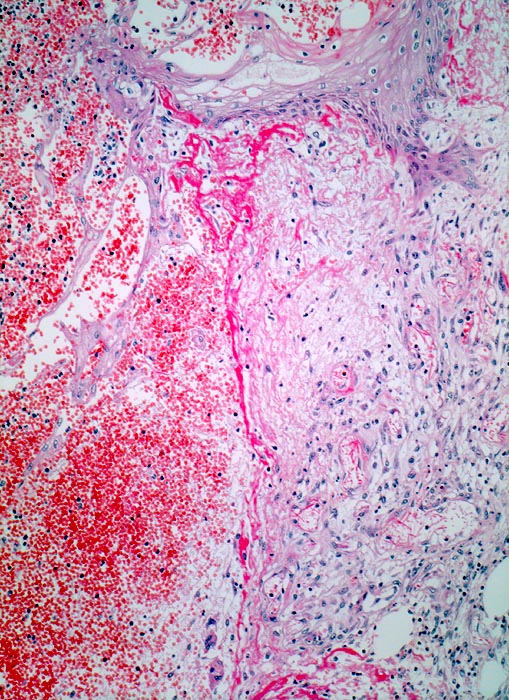

Wundheilung: Granulationsgewebe

Entzündung / Reparatur

Haut, Rumpf

Blutgefüllter spaltförmiger Defekt im Corium. Am Rand der Wunde rechts im Bild ödematöses Granulationsgewebe mit zahlreichen kapillären Gefässen, Fibroblasten und wenig Entzündungszellen. Hellrote Fibrinauflagerungen auf dem Gewebsdefekt. Neugebildete Epidermis überzieht teilweise den Wundgrund.

6 Tage alte Wunde am Abdomen nach Laparotomie.

100